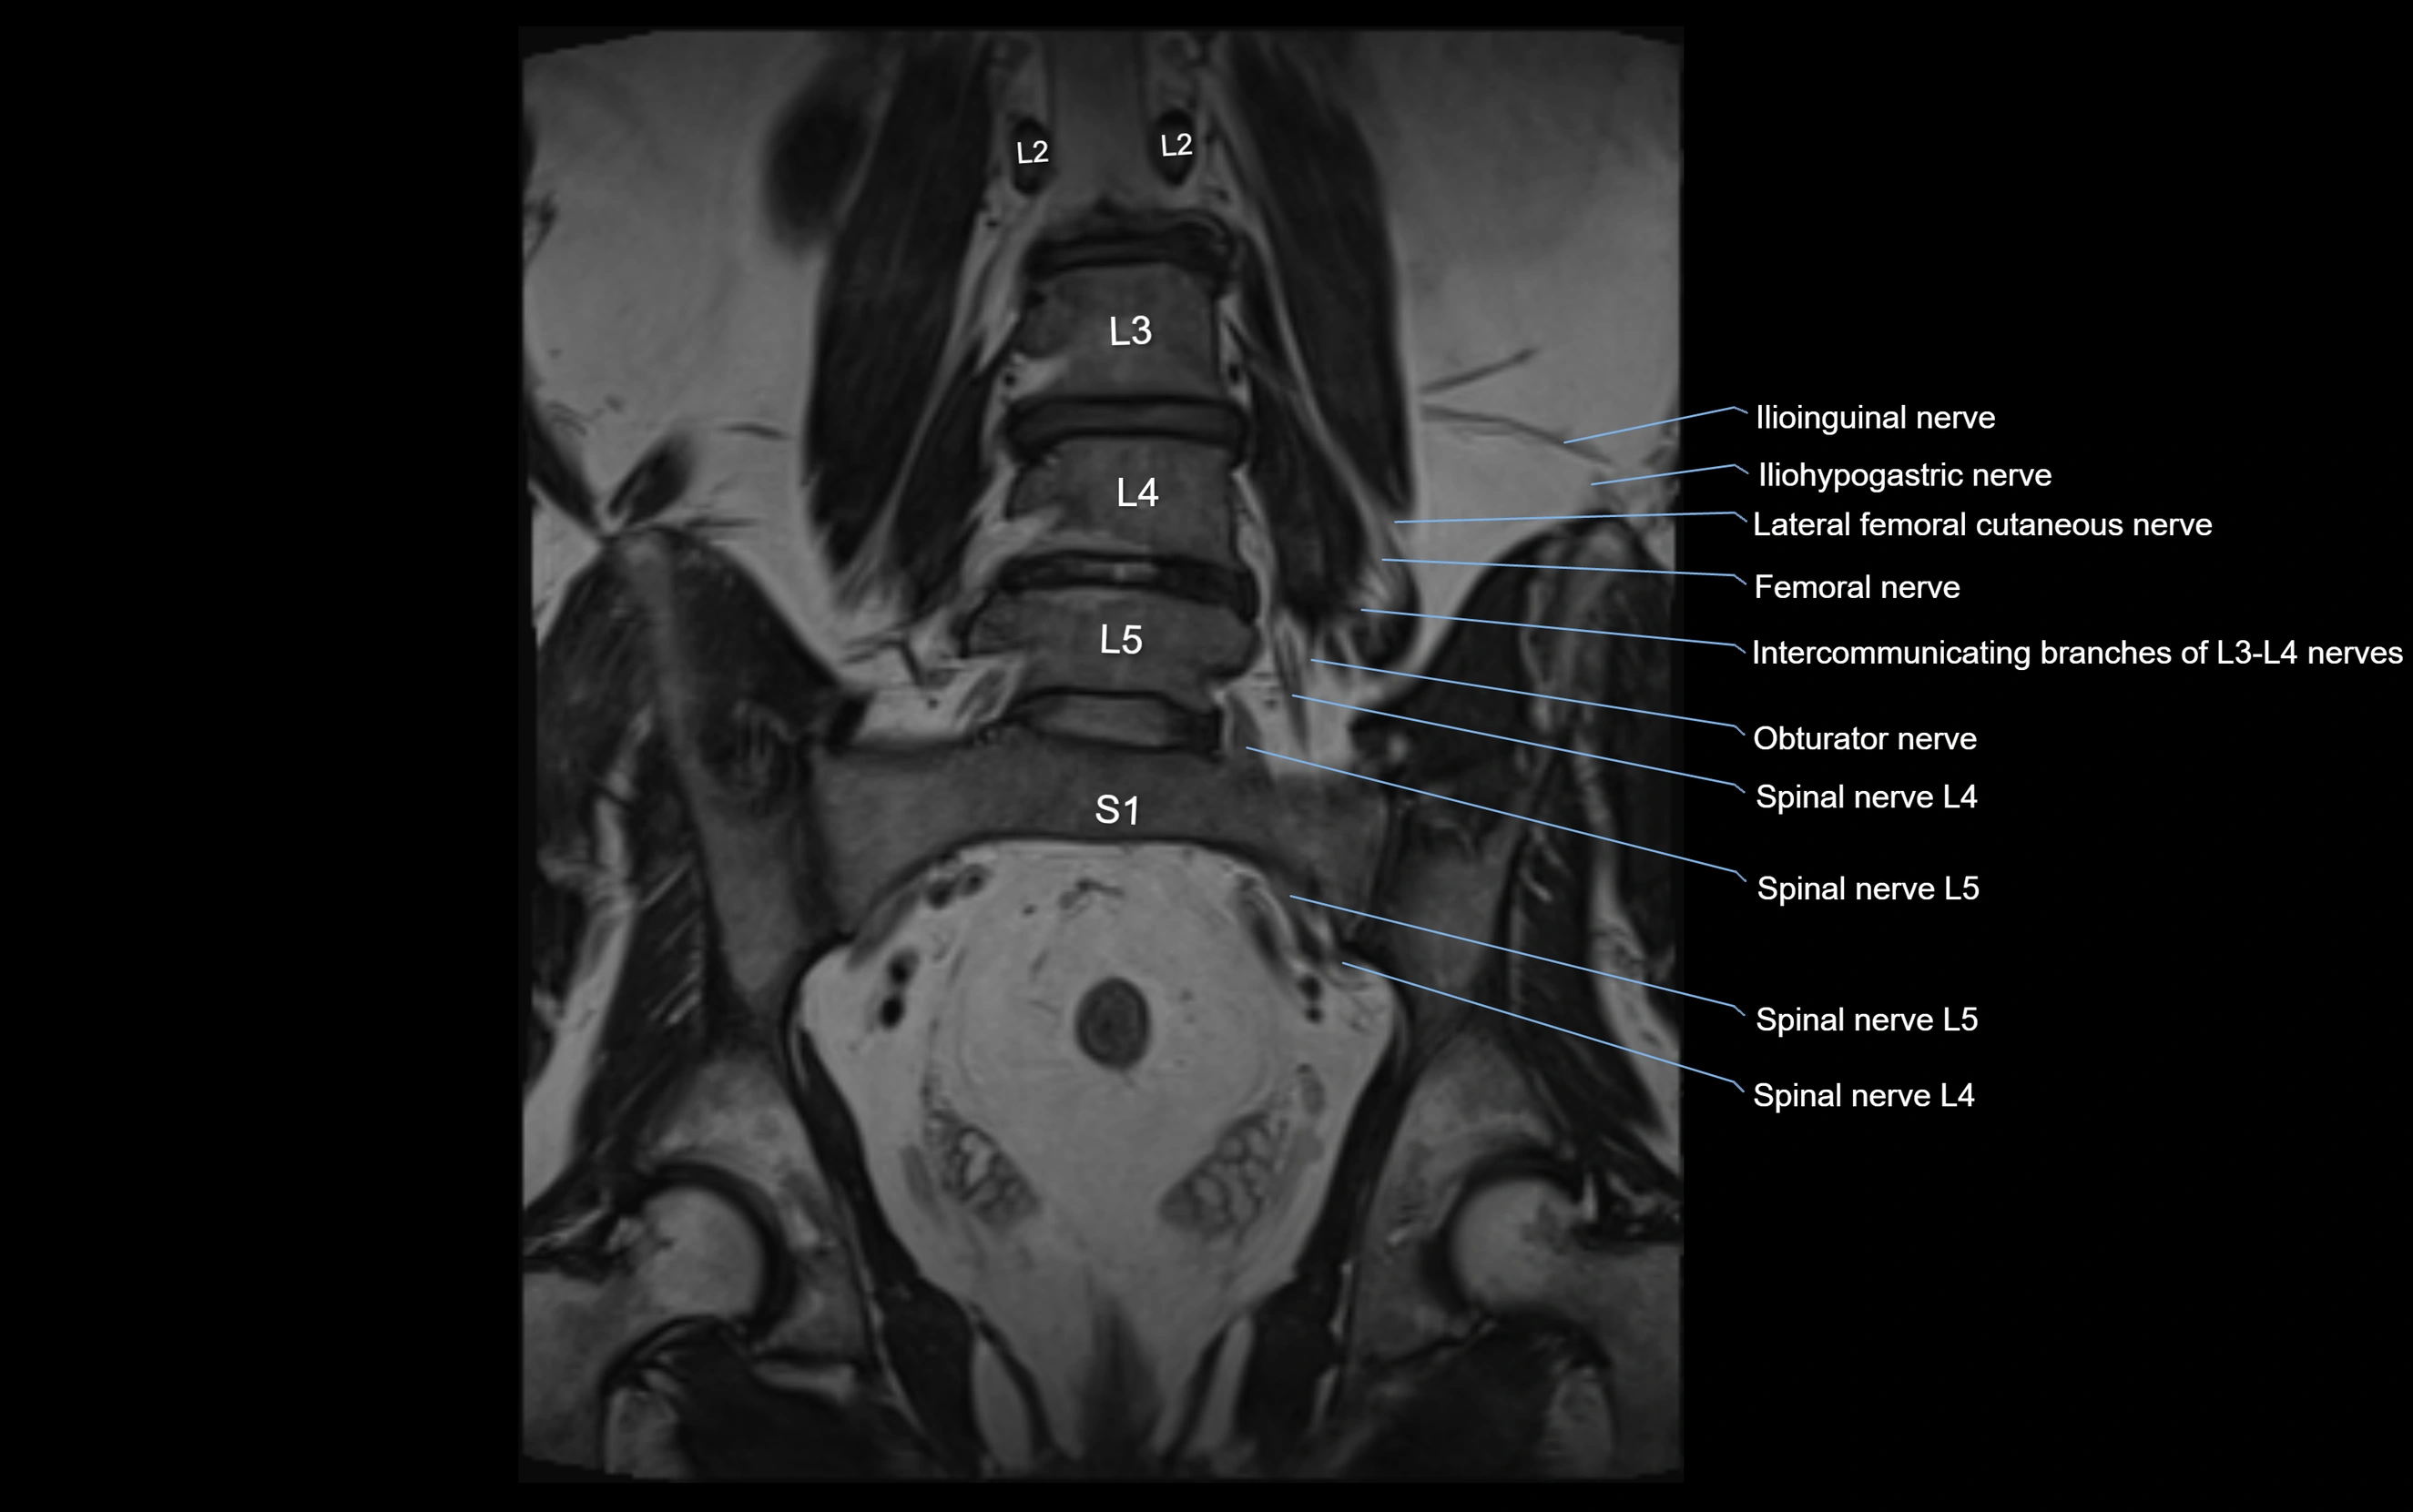

MRI Appearance

T1-weighted images:

• Nerve appears as a very thin low-to-intermediate signal intensity structure

• Surrounded by bright fat, aiding visualization

T2-weighted images:

• Nerve shows intermediate to mildly hyperintense signal compared to muscle

• Pathological involvement appears brighter

STIR (Short Tau Inversion Recovery):

• Normal nerve appears dark

• Inflamed or entrapped nerve appears bright hyperintense

T1 Fat-Sat Post-Contrast:

• Normal nerve enhances minimally

• Pathologic nerve (neuritis, entrapment, tumor infiltration) shows focal or diffuse enhancement

3D T2 SPACE / CISS:

• Nerve appears intermediate to mildly hyperintense compared to muscle

• Surrounded by bright fat or CSF, improving visualization

• Best sequence for mapping small pelvic nerves such as the anococcygeal